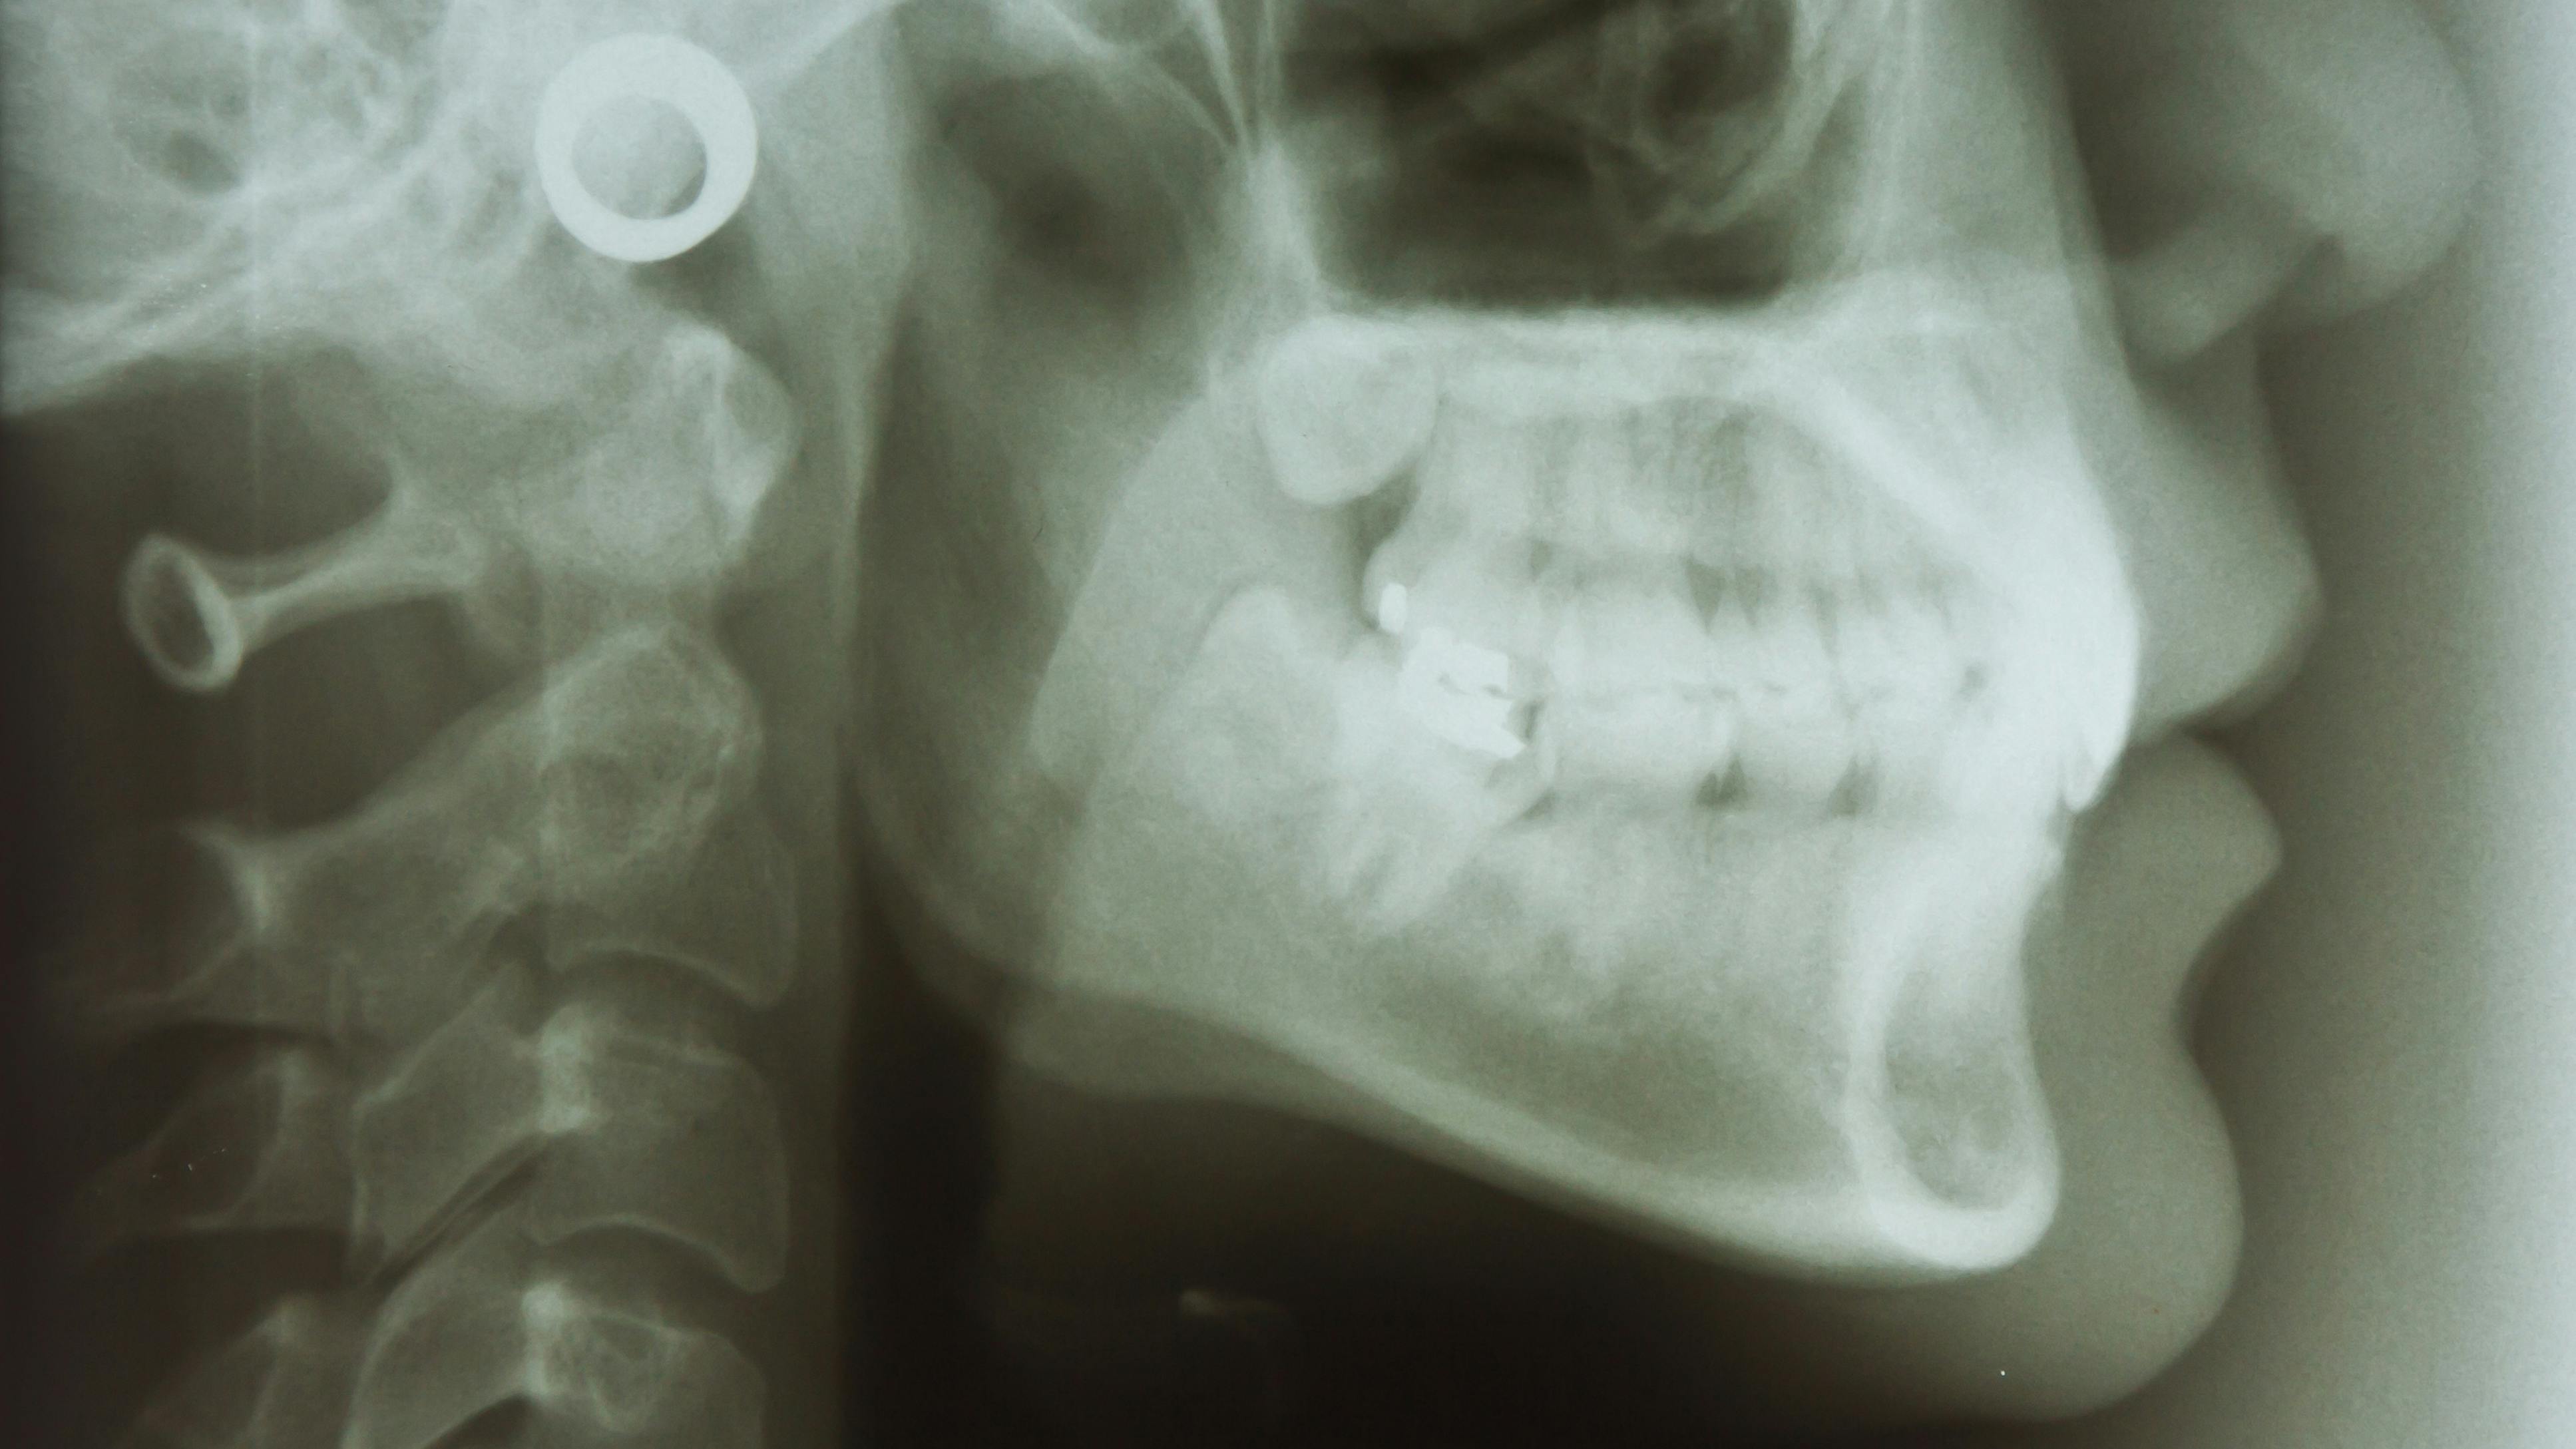

Dental hygienists can examine a patient’s tonsillar area when performing an intraoral examination.3 To see the tonsils, ask the patient to open wide while depressing the dorsal surface of the tongue.

If the tonsils look enlarged, the hygienist may want to ask the patient if they naturally have tonsils that are larger than average. If the tonsils are erythematic, displaying calcium stones (such as little white dots) or exudate, a hygienist must inform the patient.1-4

Always record any pathology notes about the tonsils (including sizes, symptoms, and colors) in the patient’s record.3 If an intraoral camera is available in the operatory, take a picture of palatine tonsils.3